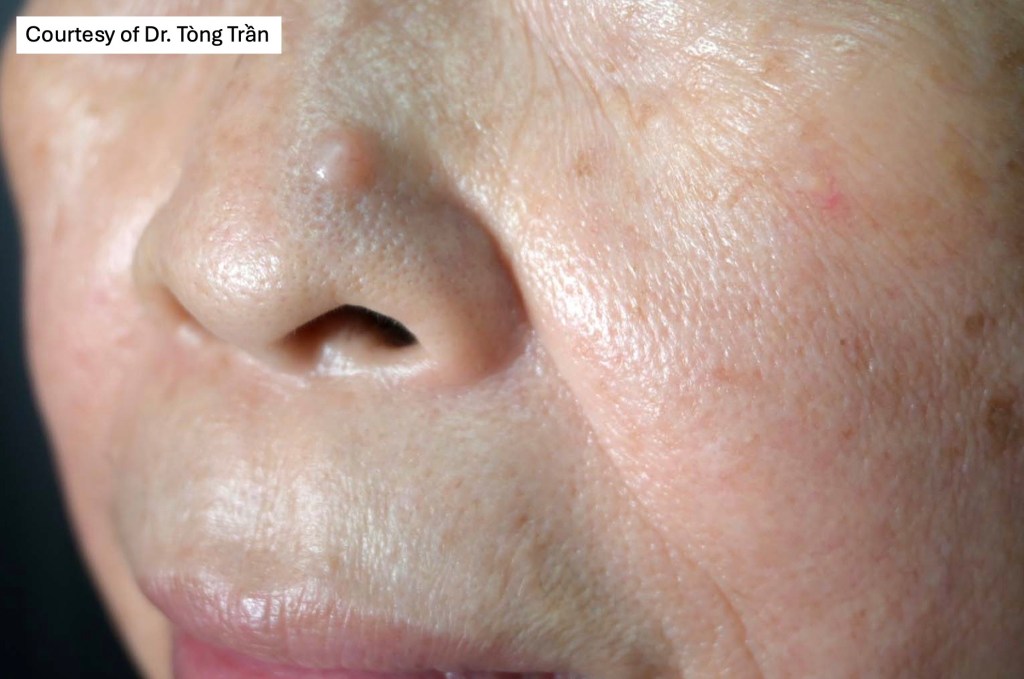

Clinical features

•Solitary trichoepithelioma presents as a flesh-colored papule or nodule (<1.0 cm) most often on the face.

•Lesions may occasionally be seen at other sites including the scalp, neck, back, vulva & proximal extremities

•Presents with symmetrically distributed numerous skin-colored papules on the naso-labial folds, eyebrows, eyelids & cheeks